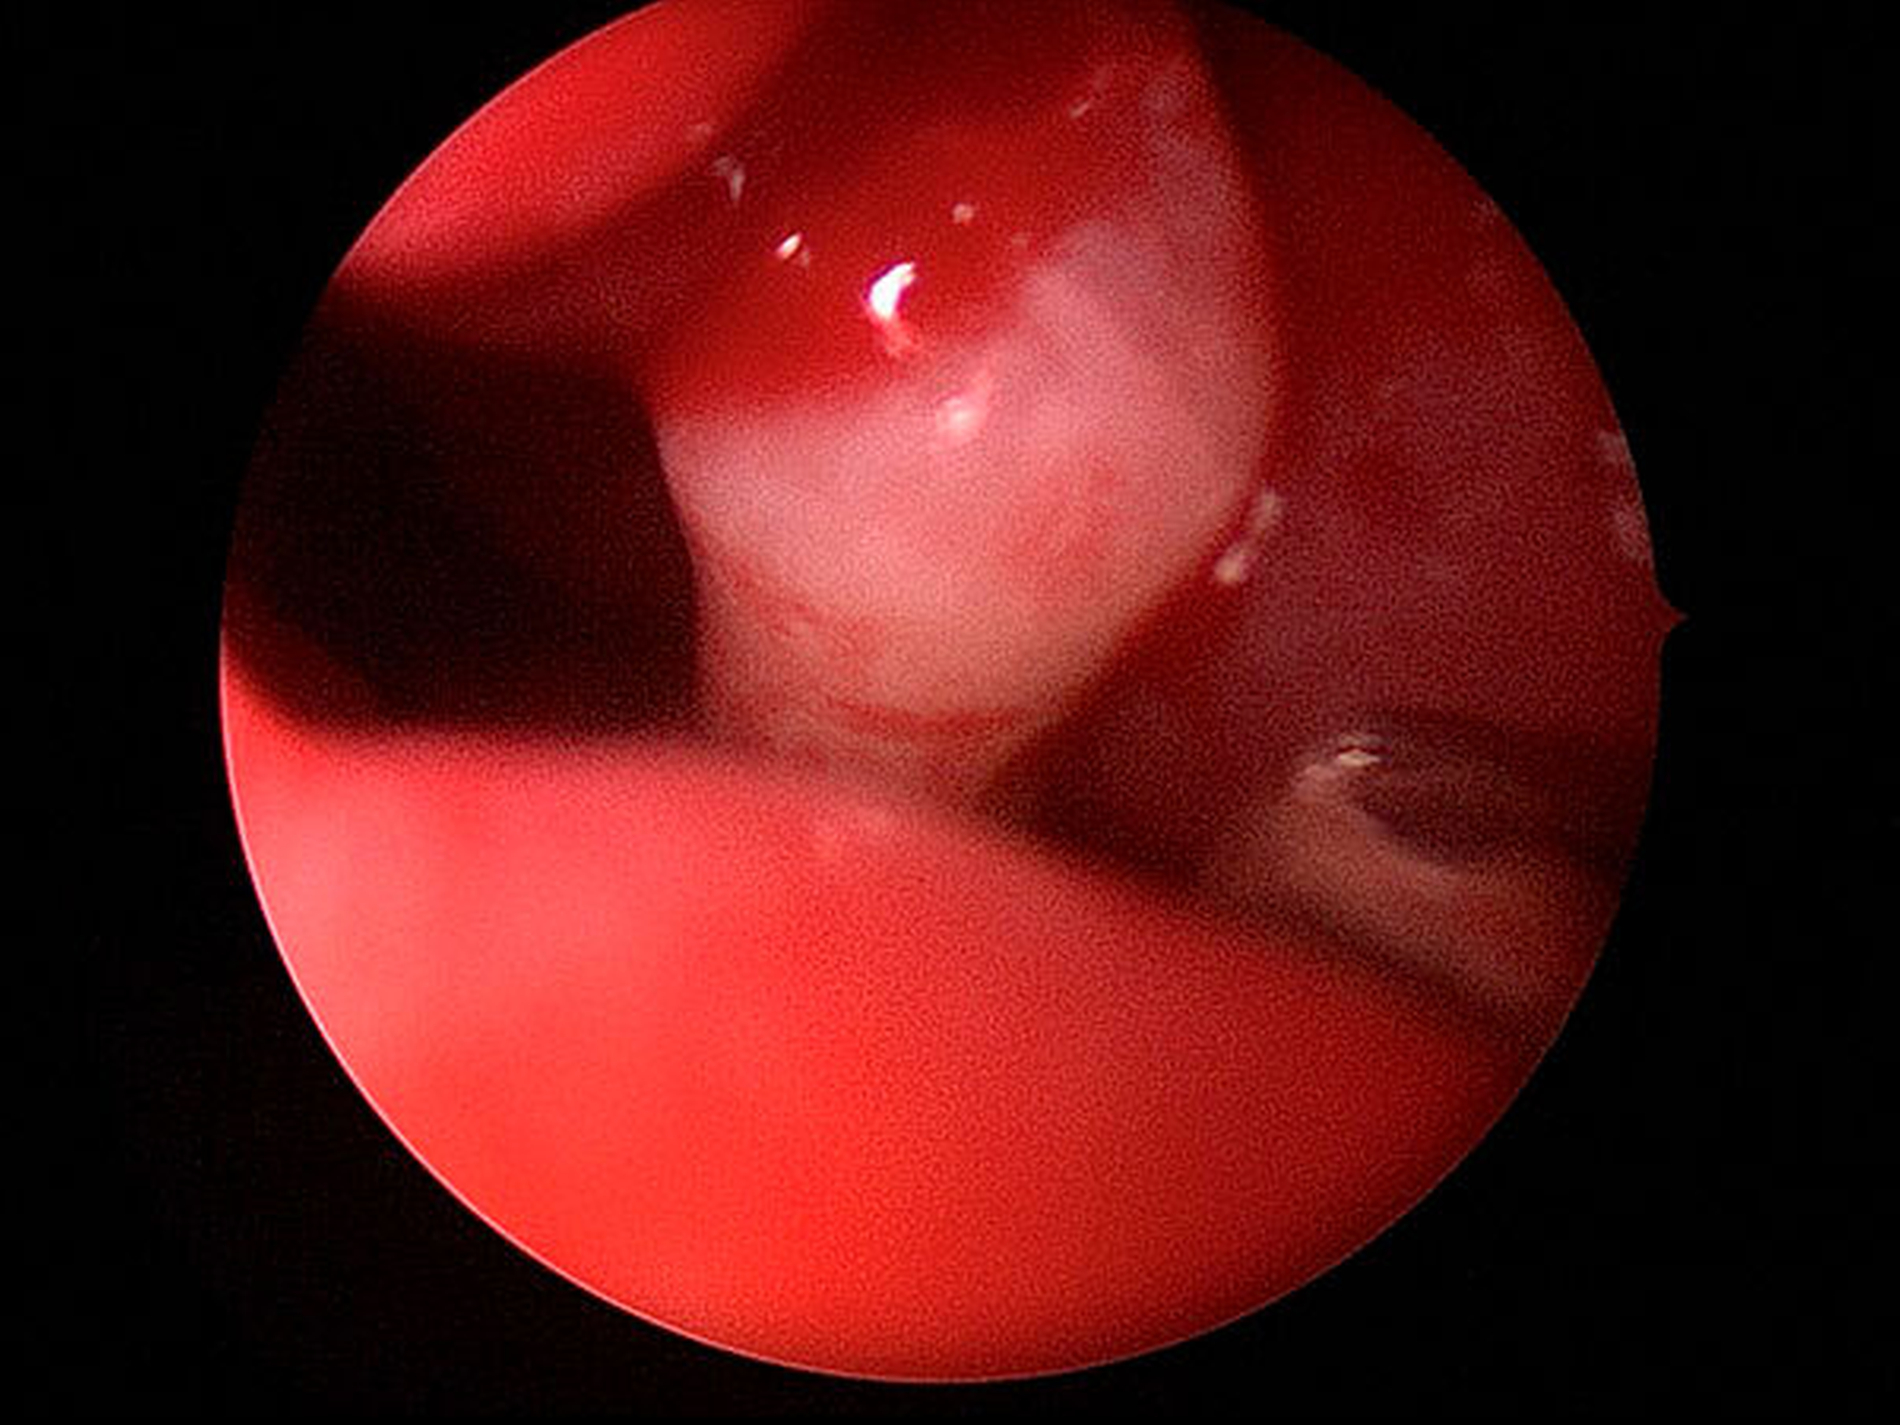

In allgemeiner Schmerzausschaltung wurde endoskopisch unterstützt eine Infundibulotomie mit nachfolgender Kieferhöhlenrevision und transnasaler Entfernung des Zahns 13a aus dem rechten Nasenboden durchgeführt (Abbildungen 3a bis 3c). Der postoperative Heilungsverlauf war komplikationslos, die definitive Histologie des entnommenen Kieferhöhleninhalts bestätigte die Verdachtsdiagnose einer chronischen Sinusitis maxillaris.